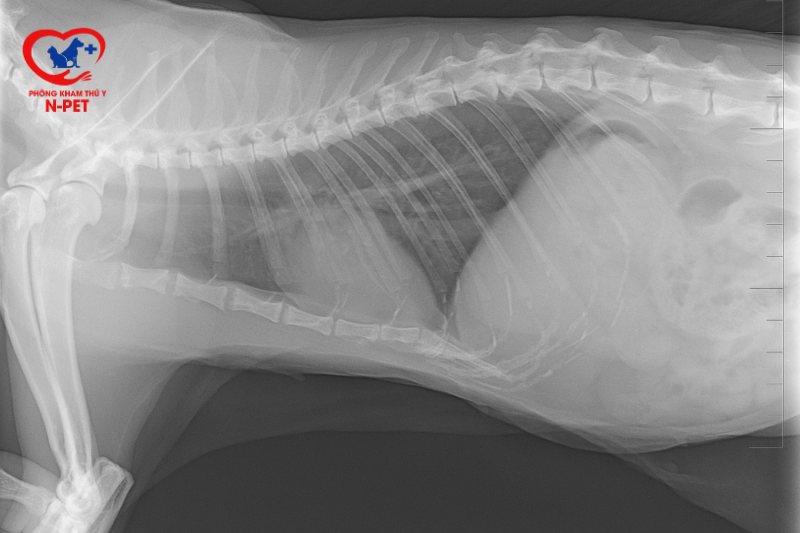

Khi mèo của bạn có dấu hiệu bị bệnh, việc chụp X-quang có thể là một bước đi cần thiết. Đây là một công cụ chẩn đoán quan trọng giúp bác sĩ thú y xác định những vấn đề nghiêm trọng như gãy xương, sự hiện diện của dị vật trong cơ thể hoặc các bệnh lý liên quan đến hô hấp. Nếu mèo bạn bị khó thở, chụp X-quang có thể giúp phát hiện ra nguyên nhân phát sinh những triệu chứng đó, chẳng hạn như bệnh tim hay tình trạng phổi.

Chụp X-quang cho mèo là một bước quan trọng trong việc chẩn đoán các vấn đề về sức khỏe, đặc biệt là khi nghi ngờ có gãy xương hoặc chấn thương. Quy trình này giúp bác sĩ thú y đánh giá tình trạng cơ xương và khớp của thú cưng, từ đó đưa ra những quyết định điều trị chính xác.

Trong quá trình chụp X-quang, mèo sẽ được đặt trên bàn chụp, ở một vị trí nhất định để đảm bảo hình ảnh rõ ràng nhất. Để có được hình ảnh chất lượng cao, bác sĩ thường sử dụng công nghệ chụp X-quang kỹ thuật số. Điều này không chỉ giúp đạt độ phân giải tốt mà còn giảm thiểu thời gian chờ đợi cho chủ nuôi.

Trong một số trường hợp, như khi mèo nuốt phải dị vật, bác sĩ có thể yêu cầu chụp X-quang với chất cản quang để quan sát đường tiêu hóa. Thăm khám lâm sàng toàn diện trước khi chụp cũng là một bước cần thiết để xác định chính xác những vấn đề mà thú cưng đang gặp phải. Tuy nhiên, để đảm bảo mèo không cử động trong quá trình chụp, thường cần phải sử dụng thuốc an thần hoặc gây mê.